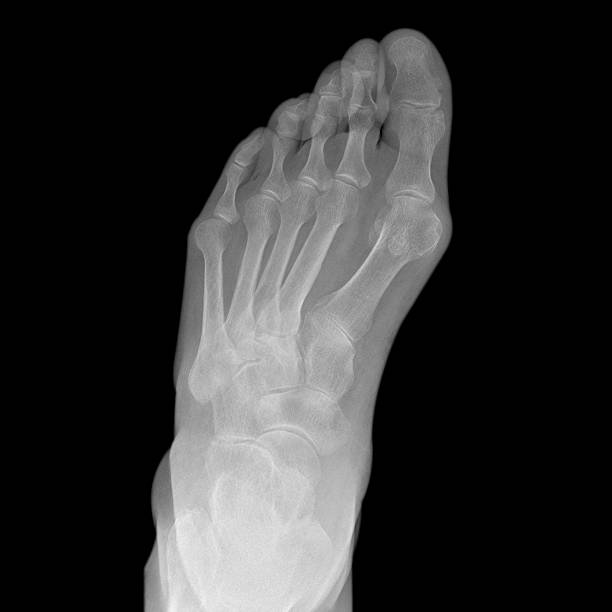

종자골염은 엄지발가락 아래쪽에 위치한 작은 뼈인 종자골(sesamoid bone)에 염증이나 통증이 발생하는 질환으로, 주로 반복적인 압력이나 충격으로 인해 발생합니다. 이 부위는 체중이 집중되는 부위 중 하나로, 보행이나 운동 시 지속적으로 자극을 받기 쉬우며, 특히 하이힐을 자주 신거나 달리기, 점프 등의 활동을 자주 하는 사람에게 잘 나타납니다. 종자골염은 초기에는 가벼운 통증으로 시작되지만, 시간이 지남에 따라 발바닥 앞쪽의 통증이 심해지고, 걸을 때 불편함을 초래하거나 발을 디딜 때 찌릿한 통증이 느껴지는 등 일상생활에 큰 영향을 미칠 수 있습니다. 본 글에서는 종자골염의 주요 원인 10가지를 중심으로, 나타나는 증상과 진단 방법, 그리고 효과적인 치료법과 재발 방지를 위한 관리법에 대해 구체적으로 살펴보겠습니다.

종자골염의 대표적인 증상은 발 앞쪽, 특히 엄지발가락 아래 부위의 통증입니다. 이 통증은 서 있거나 걷거나 뛸 때 더욱 심해지며, 장시간 활동 후에는 발바닥이 욱신거리거나 짓눌리는 느낌이 들 수 있습니다. 일부 환자는 국소적인 부기나 압통, 열감을 느끼기도 하며, 통증으로 인해 발을 절거나 무의식적으로 보행 자세가 바뀌는 경우도 있습니다. 증상이 심해지면 신발 신는 것조차 불편해지고, 심한 경우 발을 디디기 어려운 상태에 이를 수 있습니다. 특히 뻣뻣한 바닥을 맨발로 걸을 때 통증이 뚜렷해지며, 뼈를 누를 때 날카로운 통증이 느껴질 수 있습니다. 종자골염은 만성적으로 진행되는 경우가 많아 조기에 적절한 관리가 이루어지지 않으면 지속적인 통증과 활동 제한이 동반되며, 이로 인해 일상생활의 불편과 삶의 질 저하로 이어질 수 있습니다. 따라서 초기 증상을 인지하고 빠르게 대처하는 것이 매우 중요합니다.